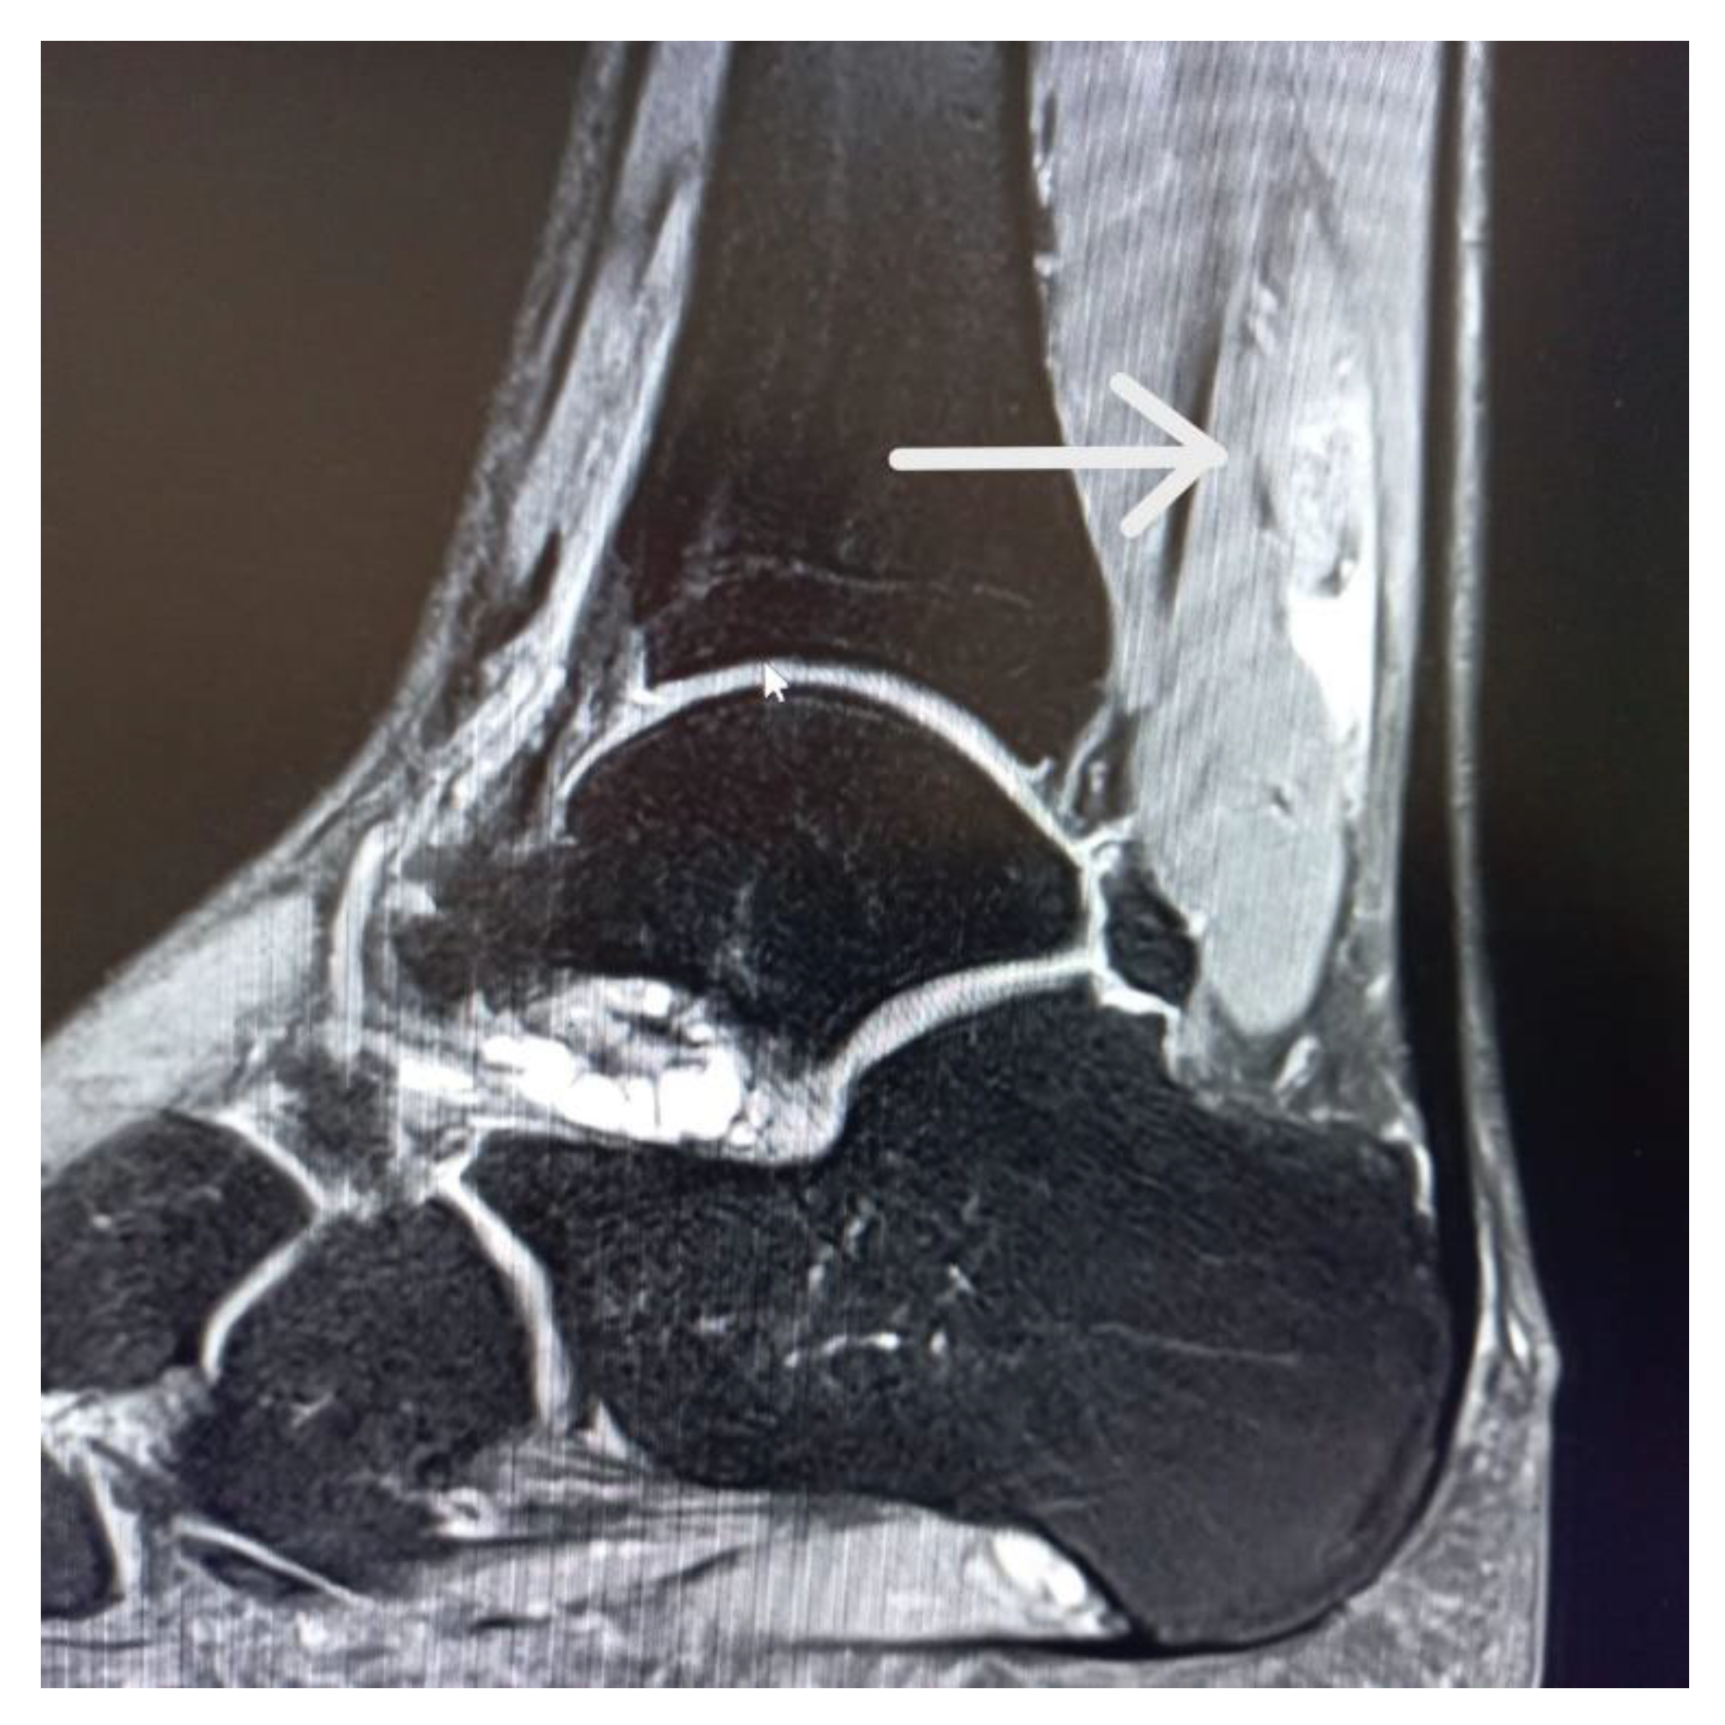

1.4. Case Report

1.5. Imaging Tests